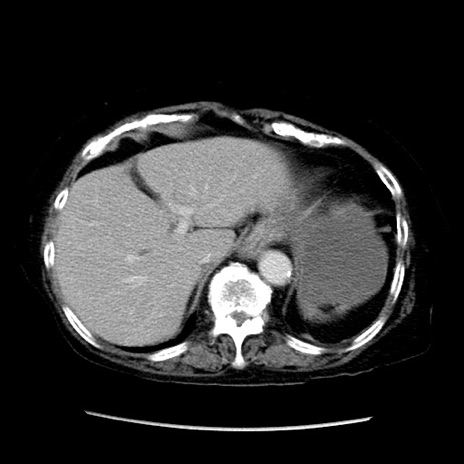

症例14(横断像)

【症例】 90歳代女性

【主訴】 腹痛・嘔吐

【現病歴】今朝から左側腹部痛を認めた。 経過観察していたが、嘔吐を認めたため来院。

【既往歴】 子宮癌術後

【身体所見】 意識清明、BP 127/54mmHg、P 98bpm Sp02 95%(RA)、BT 35.8°C、腹部平坦・軟腸ぜん動音聴取良好、右下腹部圧痛(+) 反跳痛なし

【データ】WBC 9800、CRP 0.46